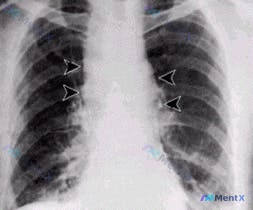

整理了一个呼吸困难查因的病例,结合胸片和临床分析,感觉这个病例的鉴别思路挺有代表性的,分享给大家。 病例核心信息 - 主诉:呼吸困难(具体时长未明确,但从影像分析推测为急性起病) - 关键影像表现(床旁前后位AP位胸片): 1. 左侧肺野中部可见局限性密度增高影,呈斑片状/结节状,边界模糊,无明显空...